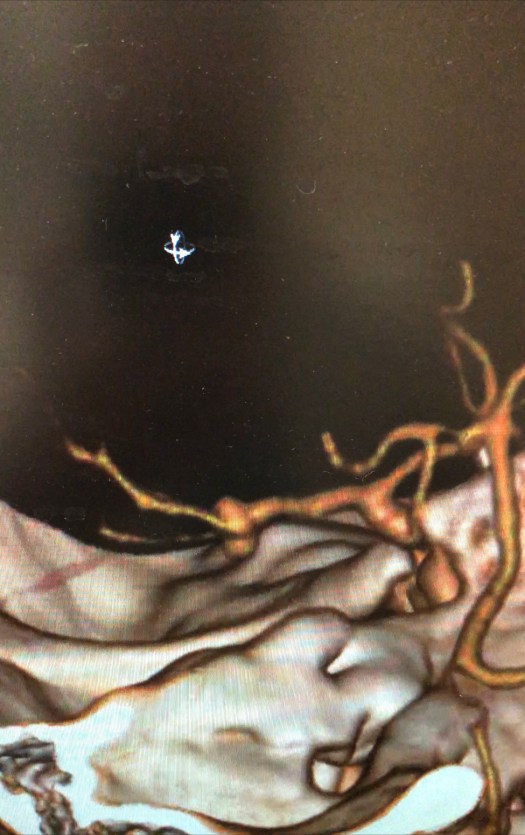

Clipping di aneurisma complesso M1-M2 di sinistra – ricostruzione biforcazione arteria cerebrale media